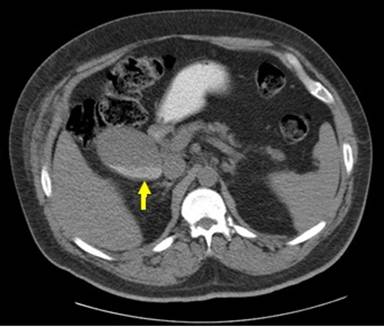

A fourty-two-year-old male with a history of poorly controlled type-2 diabetes mellitus and heart failure with coronary artery disease presented to the hospital emergency room with shortness of breath and abdominal pain. He frequently visited the emergency room for acute exacerbations of his underlying heart failure due to poor compliance with medications and dietary-lifestyle modifications, and he was taking subcutaneous insulin for diabetes control. At presentation, his glycosylated hemoglobin was 9.1% with known diabetic complications of proliferative diabetic retinopathy, peripheral neuropathy, and nephropathy (stage 4 chronic kidney disease). Physical examination revealed a diffusely tender abdomen. A CT scan of the abdomen revealed a mildly distended HGB with a maximum length of 12.2 cm and width of 9.8 cm (Figure 1), with layering of sludge and stones within the gallbladder. Contrast study was not performed in light of his chronic renal failure. The surgical team was consulted and they recommended no further intervention as he had known cholelithiasis for the prior 2 years and he had a normal sized common bile duct and the only change of note on imaging was the growth in size of the gallbladder. The abdominal pain improved spontaneously after a bowel movement. His pulmonary edema resolved with intravenous diuretics, and he was discharged with a regimen of oral diuretics. His HGB remained asymptomatic at one year of follow-up.

Figure 1. CT scan of the abdomen without contrast, transverse view, showing a distended gallbladder containing layering sludge (arrow). |